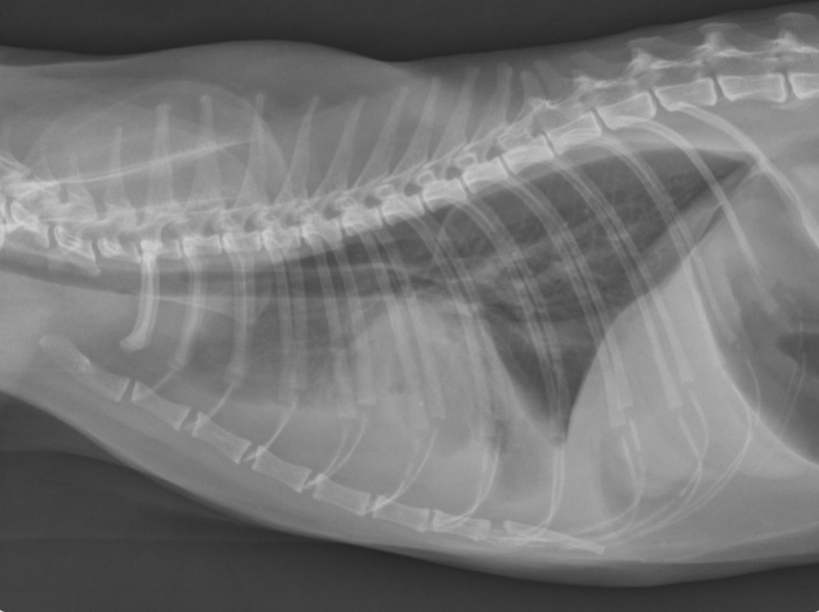

at what point is this dog in heart failure

April - pulmonary vein enlargement and beginning of lung patterns forming

July - alveolar lung patterns, big pulmonary veins